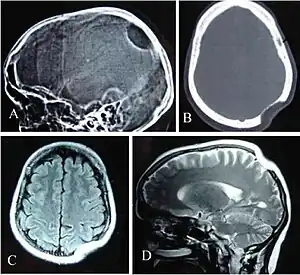

Adult-onset leukoencephalopathy

Because of the importance of the CSF1R gene in myeloid cell survival, maturation, and function, loss-of-function in both inherited copies of the CSF1R gene causes postnatal mortality. Heterozygous mutations in the CSF1R gene prevent downstream CSF1R signaling and cause an autosomal dominant neurodegenerative disease called adult-onset leukoencephalopathy, which is characterized by dementia, executive dysfunction, and seizures. Partial loss of CSF1R in adult-onset leukoencephalopathy causes microglia to exhibit morphological and functional deficits (impaired cytokine production and phagocytosis) which is associated with axonal damage, demyelination, and neuronal loss. Signaling by a DAP12-TREM2 complex in microglia is downstream of CSF1R signaling and is needed for microglia phagocytosis of cellular debris and maintenance of brain homeostasis.[18][12] TREM2 deficiency in cultured myeloid cells prevents stimulation of proliferation by treatment with CSF-1. Similarities between Nasu-Hakola disease (caused by mutations in either DAP12 or TREM2) and adult-onset leukoencephalopathy suggest partial loss of microglia CSF1R signaling promotes neurodegeneration. Defects in neurogenesis and neuronal survival are also seen in adult-onset leukoencephalopathy due to impaired CSF1R signaling in neural progenitor cells.[12]